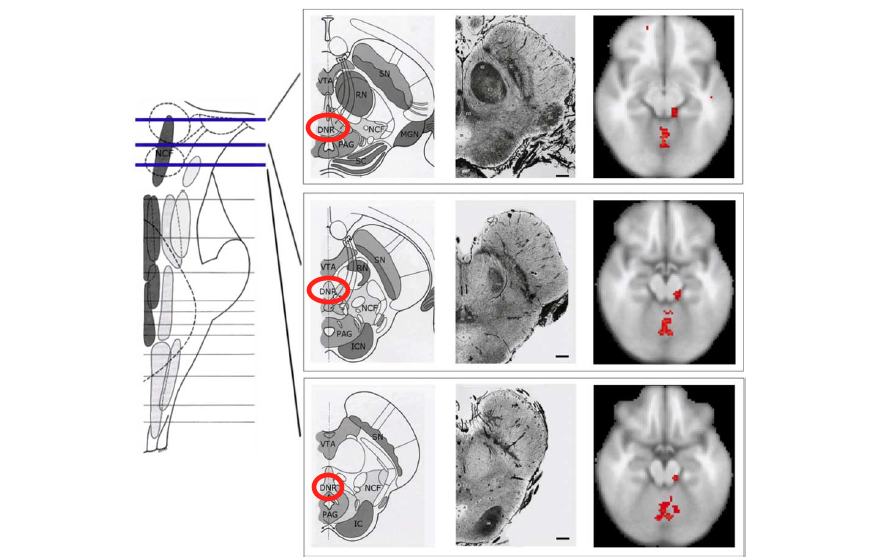

drn1